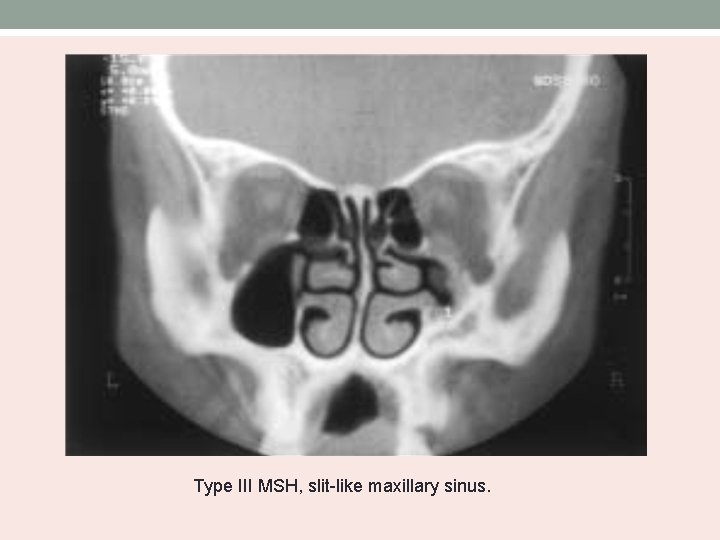

Bolger’s MSH Classification • Based on the degree of pneumatization and lateral nasal wall abnormalities. Type Uncinate process MSH I normal mild II Absent severe III Absent Cleft-like

Type III MSH, slit-like maxillary sinus.